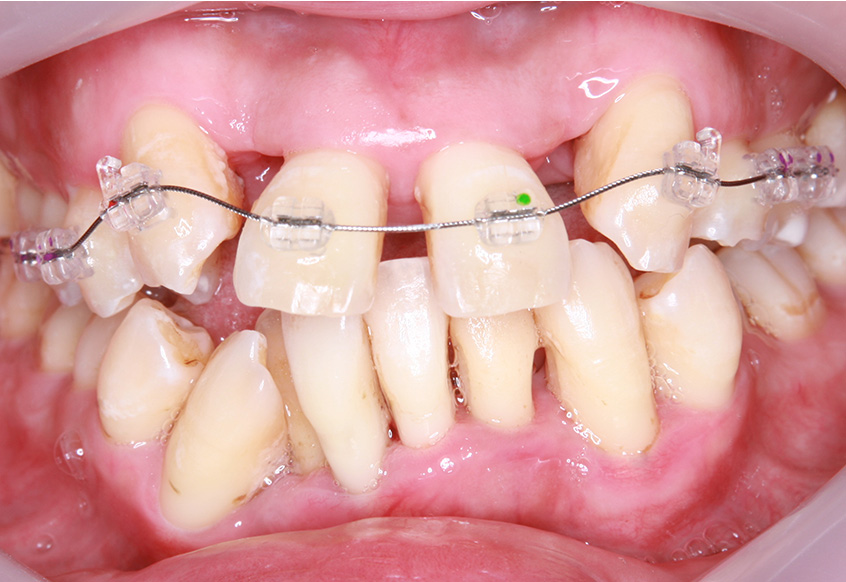

最初のお口の中 ワイヤー装着して治療を開始

-

治療開始後3ヵ月経過すると、前歯の隙間や全体の乱れが減ってきました。口笛が吹けるようになったとのことです。

最初のお口の中 治療開始3ヵ月後